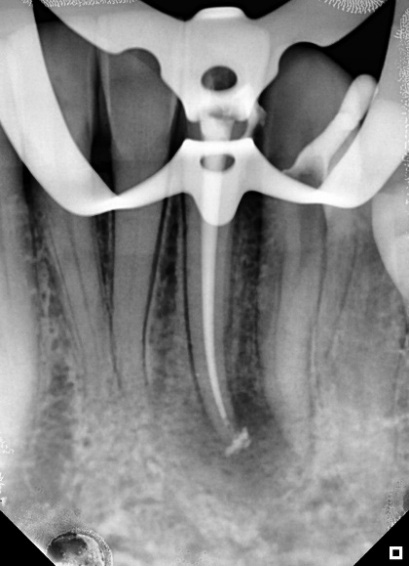

After 30 days, the patient returned and a new periapical radiograph was taken before the intracanal dressing was removed. This radiograph revealed that the periapical lesion had recovered (Figure 3). The intracanal dressing was removed with NaOCl irrigation, followed by a final rinse with EDTA and NaOCl, which was boosted with Easyclean.

Figure 3: radiographic situation after 30 days. Note the visible regression of the lesion